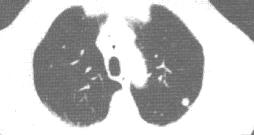

左下肺转移癌。CT平扫肺窗示左下肺边缘肺野一小结节状阴影。

②多数肺转移瘤呈结节状,可自粟粒大小至直径5cm。

④转移瘤密度均一,呈软组织密度,有5%转移瘤发生坏死而密度不均匀,甚至形成空洞。偶见转移瘤钙化,多为骨肉瘤、软骨肉瘤或粘液性结肠癌转移。